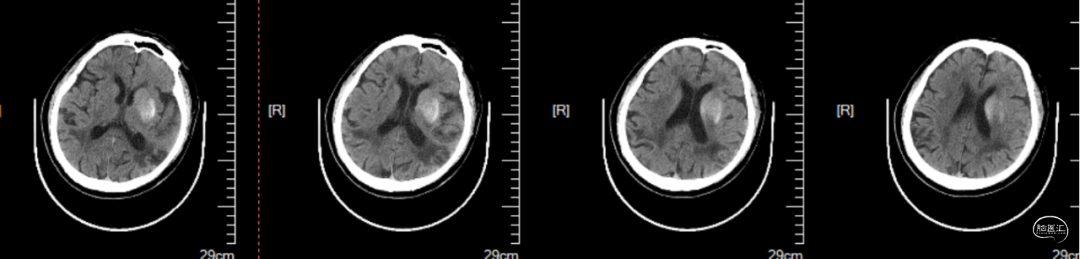

术后即刻头CT提示:梗死灶内少量造影剂强化。见图5。

图5.术后即刻头CT

术后4小时复查头CT:梗死灶内造影剂较前略吸收。见图6。

图6.术后4小时头CT